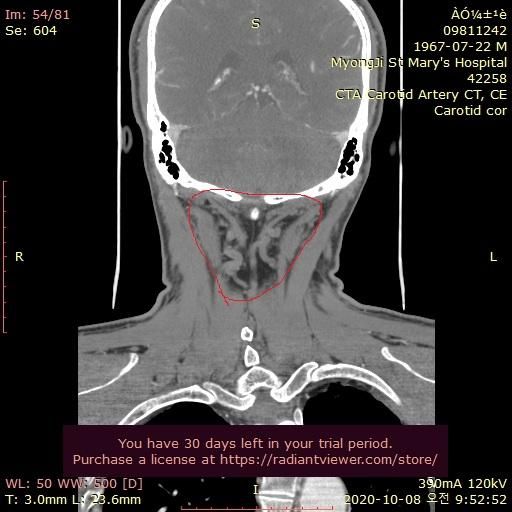

그런데 가까운 의원에서 그때의 영상을 보다가 그림과 같이 목 뒤쪽에 정맥혈관에 기형이 심한것을 알았습니다.

울퉁불퉁 하고 아주 굵어져서 혈액 순환이 안도는것으로 보입니다.

자료 찾아보니 심부경정맥 인것 같습니다. 내경정맥등과 함께 뇌의 혈액을 심장으로 빼내서 보내주는 중요한 혈관으로 보입니다.

기형이 심해서 혈액이 잘 안 빠지는 것일까요?

• 4번 째 사진